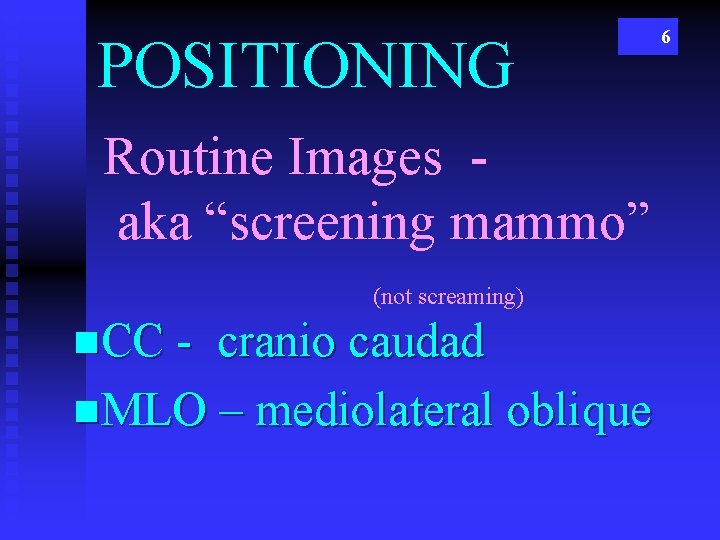

POSITIONING Routine Images aka “screening mammo” (not screaming) n. CC - cranio caudad n. MLO – mediolateral oblique 6